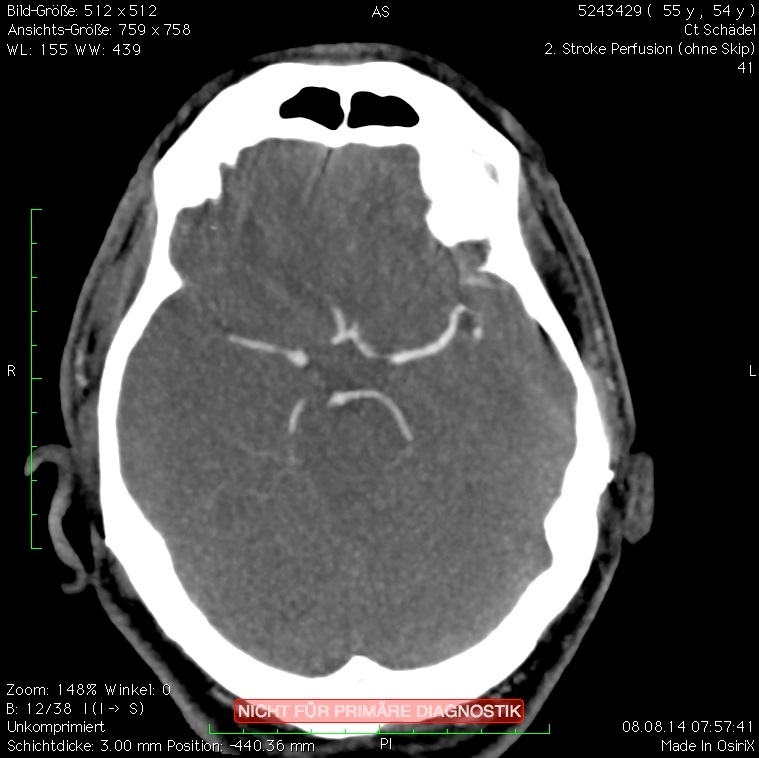

In der neuroradiologischen Versorgung von Aneurysmata werden spezielle Coils eingesetzt, die aus Platin mit Seidenanteilen bestehen – hierdurch entstehen mit herkömmlichen CTs in den Nachkontrollen massive Metallartefakte, die eine Beurteilung des Gewebes und der an das Aneurysma angrenzenden Gefäße in unmittelbarer Umgebung unmöglich machen bzw. sehr erschweren (Bild 1 a). Deutlich verbessert wird die Befundbarkeit mit SEMAR (Bild 1 b). In der postinterventionellen Kontrolle der meist intensivpflichtigen Patienten will der Kliniker in möglichst einem Untersuchungsgang komplexe Fragestellungen nach Vasospasmus/Blutung/Ischämie/Gefäßabbrüchen beantwortet haben. Diese teils hochkomplexen Fragestellungen können über die Ganzhirnperfusion in kürzester Zeit und mit hoher Detailgenauigkeit beantwortet werden. Durch die neue SEMAR-Technologie gelingt es auch, die unmittelbar an das gecoilte Aneurysma angrenzenden Gefäß und Hirnanteile in sehr guter diagnostischer Qualität darzustellen. Insbesondere die hohe Detailgenauigkeit der Gefäße war so mit herkömmlichen Geräten bisher nicht möglich und nur mittels invasiver Katheterangiografie darzustellen. Somit stellt die Kombination aus der Ganzhirnperfusion und der neuen Artefaktunterdrückung im klinischen Alltag einen enormen diagnostischen und klinischen Fortschritt und Mehrnutzen dar.

Erschwerend hat der Patient beidseitige Cochlea-Implantate (CI), so dass zum einen ausgeprägte Aufhärtungsartefakte die Diagnostik erschweren (Bild 2 a) und zum anderen eine alternative MRT-Untersuchung nicht möglich ist. In der anschließenden CT-Angiografie, als Spiral-CT gefahren, erschweren die Aufhärtungsartefakte eine genaue Lokalisation des Gefäßverschlusses (CTA Bild 2 b). In dem anschließend sekundär berechneten CTA-Datensatz (Bild 2 c) zeigt sich ein eindeutig zu diagnostizierender Verschluss der rechten A. cerebri media im M2-Segment als Ursache für die linksseitige Hemiparese. Die in der CTA noch ausgeprägten Aufhärtungsartefakte werden nach der SEMAR-Rekonstruktion deutlich reduziert, so dass hieraus auf vergleichbaren Schnittebenen ein klarer diagnostischer Zugewinn resultiert (Vergleich Bild 2 b und Bild 2 c). Zusätzlich kann in diagnostischer Qualität eine Ganzhirnperfusion errechnet werden, so dass die Frage nach einem Perfusionsmismatch ebenfalls beantwortet werden kann.